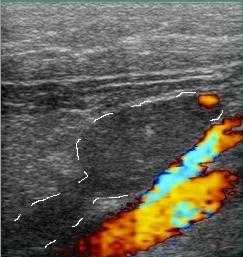

Повышения вязкости крови ведет к появлению эхогенности внутрисосудистого содержимого. Стенка у вен намного тоньше артериальной, и в норме всегда меньше 1 мм, не имеет деления на слои. Артериальная хорошо видна, дифференциация на слои отчетливая. При обследовании вен оценивают ее стенку, диаметр просвета, однородность просвета, внутрипросветные структуры, реакцию на функциональные пробы, как в черно-белом режиме, так и с цветовым кодированием кровотока. При проведении проб, на вдохе вены расширяются, работоспособные клапаны не пропускают кровь в противоположном направлении (от сердца к периферии), что отражается при цветовом кодировании кровотока как отсутствие цвета, в патологии же, цвет меняется на противоположный.

Определяется наличие или отсутствие рефлюкса, диаметр вен. Расширение большой подкожной вены более 7

мм на бедре, и малой подкожной в подколенной ямке более 4 мм в положении стоя является признаком

варикоза и сопровождается клапанной недостаточностью.

Главные показатели их - диаметр и направленность потока крови. Не всякая расширенная вена имеет

рефлюкс, и не всякая вена с рефлюксом расширена.